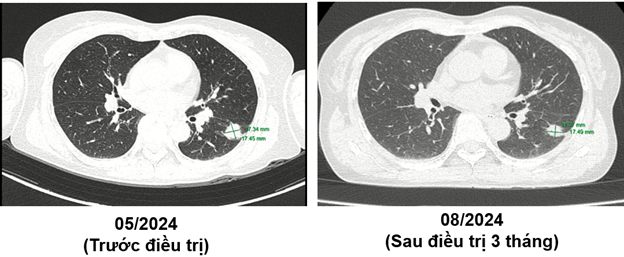

CT ngực (05/2024):

Hình 2: Hình ảnh tốt đặc ở phân thùy S6 phổi trái, đường kính 17 mm, bờ tua gai. Không thấy hạch trung thất to.

Ct ngực sau điều trị:

Theo dõi định kỳ bằng lâm sàng, chụp CT ngực và MRI sọ não sau 3 tháng, 6 tháng và 15 tháng cho thấy:

- Tổn thương phổi và não giảm kích thước rõ rệt.

- Không xuất hiện tổn thương di căn mới.

- Tình trạng toàn thân ổn định, chất lượng sống được cải thiện.